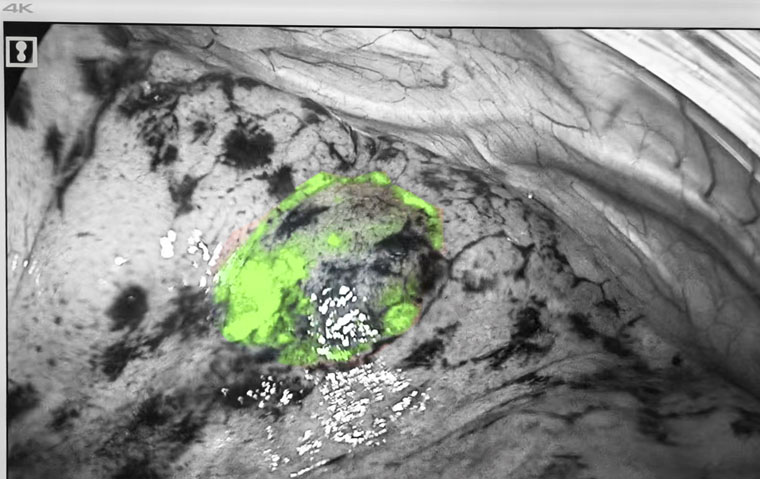

熒光顯影標記

手術在麻醉三科賈麗主任團隊全程保障及東院手術室護理團隊的協助下進行。黃超主治醫師操作電磁導航支氣管鏡,胸科內鏡室張金澤技師長、邊媛媛主管護師全力配合。患者全麻后,醫療團隊經氣管插管進鏡,在電磁導航的實時指引下分別到達兩處病灶位置,并將熒光顯影劑通過內鏡鞘管分別滴注至兩處病灶定位標記,整體操作時間僅10余分鐘。定位后,胸腔鏡手術隨即進行。熒光模式下,在肺表面即可看到定位的熒光顯影標記,術者對病灶進行精準切除。術中快速冰凍病理顯示,右肺上葉前段楔形考慮微浸潤性腺癌,肺上葉后段楔形肺組織內可見纖維化結節,周邊局灶肺泡上皮非典型增生,最終石蠟病理回報吻合口切緣陰性,表示邊緣未發現腫瘤細胞,手術已完整切除病變。